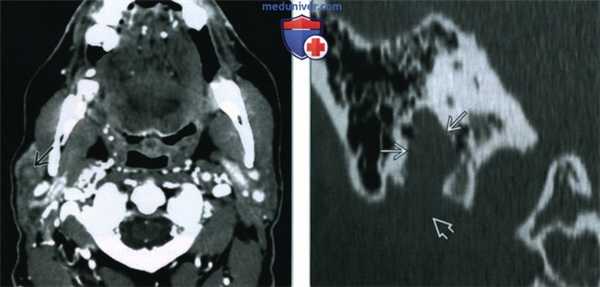

(Слева) МРТ Т1ВИ FS с КУ, аксиальная проекция. У переднего края поверхностной доли правой околоушной железы определяется округлое образование 0. Имеются участки неоднородного накопления контраста с включениями кист. Обратите внимание, что закупорка выводного протока опухолью привела к развитию паротита.

(Справа) МРТ Т2ВИ FS, аксиальная проекция. Визуализируется округлое образование с неоднородным сигналом высокой интенсивности, которое расположено в области переднего края поверхностной доли околоушной железы. Отличить такое образование от доброкачественной смешанной опухоли, которая встречается гораздо чаще, практически невозможно. (Слева) КТ с КУ, аксиальная проекция, выполненная у пациента с нейрофиброматозом 2 типа. В области переднего края поверхностной доли околоушной железы имеется округлое образование размером менее 1 см. Шваннома неравномерно накапливает контраст, но из-за небольших размеров участки кистозного перерождения отсутствуют.

(Слева) На аксиальной МРТ (Т1 ВИ С+ FS) в передних отделах поверхностной доли околоушной железы визуализируется округлое объемное образованней Опухоль неравномерно накапливает контраст, видны разбросанные кистозные участки. Обратите внимание на паротит обусловленный обструкцией протока шванномой.

(Справа) На аксиальной MPT (Т2 ВИ FS) в передних отделах поверхностной доли околоушной железы визуализируется опухоль округлой формы с неоднородным гиперинтенсивным сигналом. Такое новообразование сложно отличить от значительно более частой доброкачественной смешанной опухоли.

(Слева) На аксиальной КТ с КУ у пациента с нейрофиброматозом 2 типа в передних отделах поверхностной доли околоушной железы визуализируется округлое объемное образование субсантиметрового диапазона. Эта шваннома неравномерно накапливает контраст, кистозные участки в ней отсутствуют из-за малого размера.

(Справа) Накорональной КТ в костном окне определяется равномерное вздутие вертикального сегмента лицевого канала. Шваннома лицевого нерва поднимается через околоушную железу к шилососцевидному отверстию.

(Справа) МРТ Т2ВИ FS, аксиальная проекция. Визуализируется округлое образование с неоднородным сигналом высокой интенсивности, которое расположено в области переднего края поверхностной доли околоушной железы. Отличить такое образование от доброкачественной смешанной опухоли, которая встречается гораздо чаще, практически невозможно.

(Слева) КТ с КУ, аксиальная проекция, выполненная у пациента с нейрофиброматозом 2 типа. В области переднего края поверхностной доли околоушной железы имеется округлое образование размером менее 1 см. Шваннома неравномерно накапливает контраст, но из-за небольших размеров участки кистозного перерождения отсутствуют.

(Справа) КТ в коаном окне, коронарная проекция. Вертикальный сегмент канала лицевого нерва расширен. Шваннома лицевого нерва из облааи околоушной железы распроараняется в шилососцевидное отвераие.